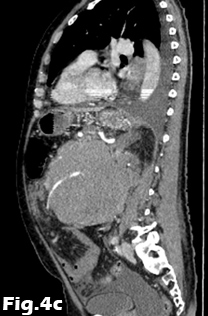

We present the case of a 59-year-old male, previously fit and well who presented to the General Practitioner with a 3 week history of epigastric pain, shortness of breath and unintentional weight loss. On examination, there was evidence of abdominal distension and palpable swelling of left testes. Initial investigation with US of the scrotum revealed dilated (maximally 5.3mm) left pampiniform plexus with retrograde flow on Doppler ultrasound and Valsalva manoeuvre, consistent with an extensive unilateral varicocele (Fig. 1 and 2). Subsequent abdominal ultrasound demonstrated moderate ascites, dilated common bile duct, large right sided pleural effusion and a large 14x14cm solid, vascular epigastric mass. This prompted urgent surgical referral and further cross-sectional imaging (Fig. 3). CT abdomen showed a large soft tissue density retro-peritoneal mass obliterating the portal mesenteric vein circulation and causing the left varicosity (Fig. 4). Ultrasound guided biopsy of the central abdominal mass confirmed a Stage IV Mantle cell Lymphoma.

Figure 4: Contrast-enhanced CT of the abdomen demonstrating the retro-peritoneal mass. Axial images (A, B) of the retro-peritoneal mass encasing the superior mesenteric artery. Sagittal reformatted image (C) of the retroperitoneal mass demonstrating the superior mesenteric artery encasement, the extent of the mass and pleural effusion. Coronal reformatted image (D) of the retroperitoneal mass. Note is made of fluid in the perihepatic space and within the pelvis.